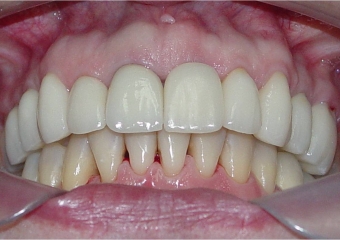

Imagem final, do caso terminado em Maio de 2013

Sorriso final